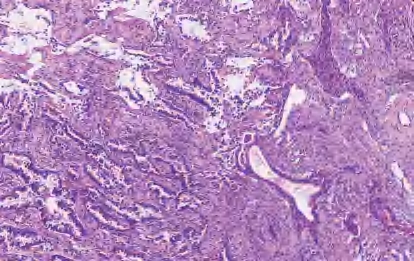

【镜下形态】腺鳞癌由腺癌和SCC两种成分混合组成,在腺癌成分中可以看到任何组织学类型的腺癌,SCC成分可以是角化性或非角化性亚型。如果每种癌成分都分化良好,则诊断腺鳞癌并不困难,不需要通过免疫组织化学来诊断(图2-10)。如果肿瘤具有部分实性腺癌成分或非角化性SCC成分,则诊断更加困难。如果两种肿瘤成分是离散的,则诊断相对容易;如果它们合并混合,则诊断相对困难。腺癌的最佳免疫组织化学标志物是TTF-1,SCC的最佳免疫组织化学标志物是p40。由于10%~20%的肺腺癌TTF-1表达呈阴性,所以有时可能需要做黏蛋白染色来确认TTF-1阴性的实性成分中是否有腺癌分化。如果存在少量腺癌成分,但其比例未达到10%,也应在报告中注明,因为无论腺癌比例如何,肿瘤都可能携带腺癌相关的驱动基因突变。要明确两种肿瘤成分,取材范围至关重要。对于<3 cm的肿瘤,宜对整个肿瘤进行取样;对于较大的肿瘤,每1 cm至少取一个切片。腺鳞癌的诊断需要基于手术切除标本,小活检或细胞学标本检查不能直接作出腺鳞癌的诊断,仅能提出建议。

图2-10 腺鳞癌